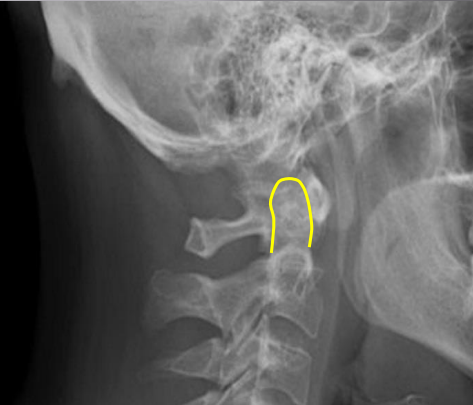

Junction of lamina (top of spinous)

Uncinate processes

Inferior aspect of vertebral bodies